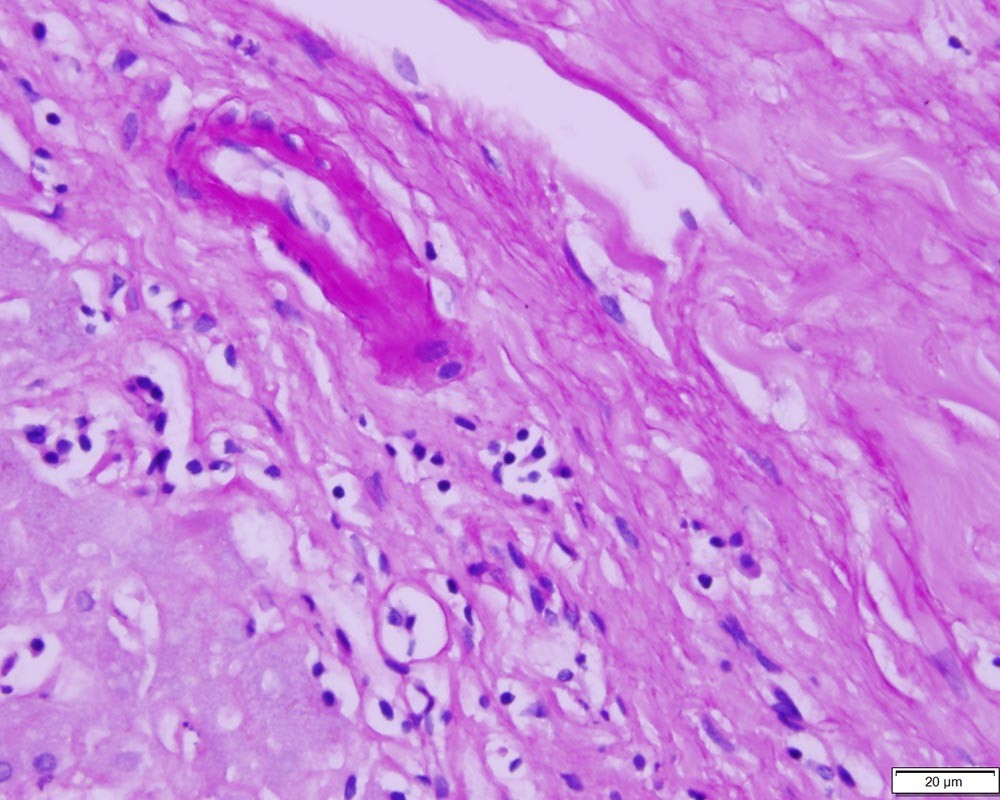

My initial testing of the Azer Scientific Control SLIDE, Glycogen ESCS-116 took place in our pathology lab, integrated directly into our routine glycogen staining procedures. We included one control slide in each batch of patient samples undergoing Periodic acid–Schiff (PAS) staining with diastase digestion. This allowed us to assess the stain’s effectiveness in both highlighting and removing glycogen.

The slides performed consistently well under standard laboratory conditions. We maintained a controlled temperature and humidity, and followed established staining protocols precisely. The stain adhered uniformly to the control section on the slide, exhibiting a distinct and easily interpretable color reaction, indicating successful glycogen detection.

The first-time use revealed no immediate issues or surprises. The control slides integrated seamlessly into our workflow and provided a clear, reliable benchmark for evaluating stain performance. The positive charge on the slide ensured that the tissue sections adhered well throughout the staining process, preventing detachment and maintaining the integrity of the sample.